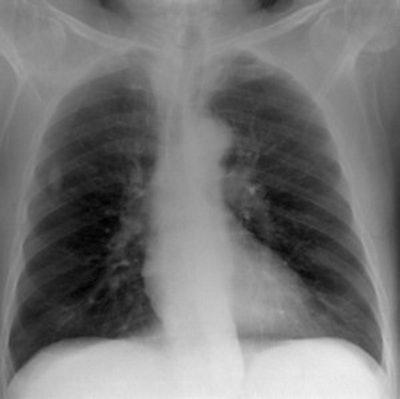

Top: Digitally reconstructed radiograph (DRR) of a chest x-ray reconstructed with a tube potential of 50 kVp. Below: DRR of a chest x-ray reconstructed with a tube potential of 150 kVp. Bottom: DRR of a chest x-ray reconstructed with an antiscatter grid. There is increased detail in the spine and diaphragm region. All images courtesy of Craig Moore.

The model was validated with a phantom and patients; it provided predictions of signal-to-noise ratios, tissue-to-rib ratios, and pixel value histograms that lie within the range of values measured with patients and the phantom. The maximum difference in measured signal-to-noise ratios to that calculated was 10%. Tissue-to-rib ratio values differed by a maximum of 1.3%.

They found anatomical noise was adequately simulated using human chest CT datasets. Scatter and system noise was successfully added post-DRR calculation, which resulted in signal-to-noise ratios, tissue-to-rib ratios, and pixel value histograms that are in good agreement with those measured in CR-acquired images.

"Although DRR resolution is not as good as real CR images, four independent expert image evaluators believe DRR images adequately simulate real radiographs and provide realistic anatomical features. Therefore, this computer model provides us with a tool that can be used by radiologists to grade quality for images derived with different x-ray system parameters, without the need to perform repeat exposures on patients," they wrote.